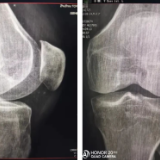

尿毒症维持血透的张师傅,一直都没有高尿酸血症,但最近遇到一个不小的麻烦,膝关节疼痛剧烈,并有肿胀、发热,不能正常行走,一度有放弃血透的念头。这一住院才发现得了晶体性关节炎。晶体性关节炎,顾名思义就是结晶体沉积在关节软骨及其周围组织所导致的关节局部炎症,严重时可导致发热、乏力、食欲减退等全身炎症表现,影响患者生活。

大家熟知的晶体性关节炎就是尿酸盐沉积在关节内所导致的痛风,其实结晶体除了尿酸盐结晶,还有焦磷酸盐结晶、碱性磷酸钙结晶(羟磷灰石)等。上述晶体性关节炎所导致的临床表现有诸多相似性,但鉴别诊断需要依据病程、既往病史、实验室和影像学检查以及受累关节作出初步判断,诊断金标准需要通过偏振光显微镜下检查关节液来进行确诊。在偏振光显微镜下,单尿酸钠晶体呈针状,具有很强的负双折射性。焦磷酸钙晶体呈多态性并显示出弱的正双折射。

尿毒症患者之所以容易出现晶体性关节炎,主要与甲状旁腺功能亢进,导致钙磷代谢失调,当钙磷浓度超过了羟磷灰石结晶溶解度,即促进结晶体的形成。另外,血液透析患者,血浆焦磷酸盐浓度下降,也促进了血管、关节软骨的钙化。